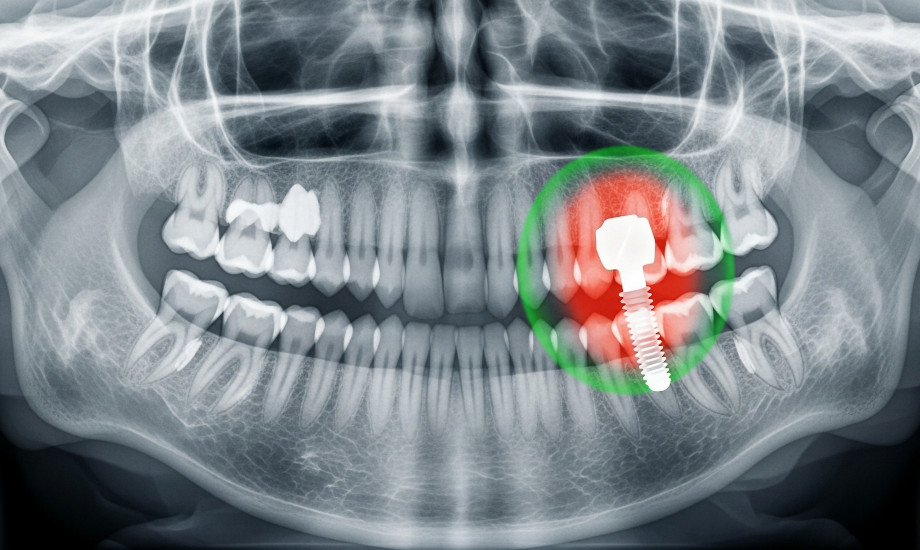

Welchen Einfluss hat der Vitamin-D-Spiegel auf die Einheilung von Zahnimplantaten? Welche „Überlebensrate“ haben Zahnimplantate bei normwertigem Vitamin-D-Spiegel? Diese und weitere Fragen soll eine nun veröffentlichte Leitlinie beantworten.